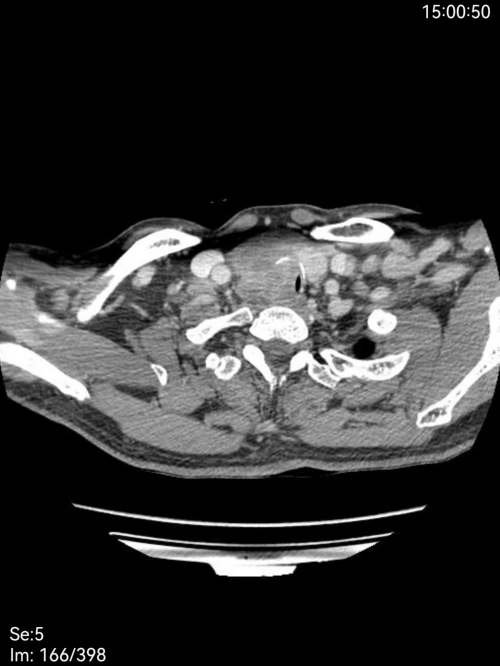

治疗前

治疗后

经过两个月的规范治疗,9月5日患者复查时,影像学检查显示肿瘤体明显,电子鼻咽喉镜证实气道通畅,赵龙珠主任团队为其拔除气管套管并封闭造瘘口,患者恢复自主呼吸。